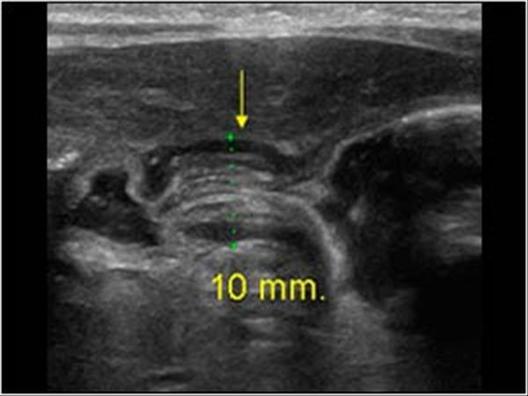

Çocukluk çağlarında karın ağrısı en sık şikayetlerden birisidir. Hayatın ilk 6 ayında en sık karın ağrısı sebebi bağırsak gelişiminin henüz tam olarak tamamlanmadığı için oluşan kolik ağrılardır. Bu durum hemen hemen her bebekte görülmekle birlikte rutin bir karın ultrasonu ile bebekte karın ağrısı sebebi olabilecek başka problem olmadığının teyit edilmesi gerekmektedir. Yine hayatın erken dönemlerinde daha sıklıkla karşılaştığımız bir diğer karın ağrısı sebebi invajinasyondur. Bu durumda bağırsak iç içe girer. Eğer kendiliğinden ya da medikal tedavi ile açılmazsa cerrahi olarak bu lokalizasyondaki problemin çözülmesi gerekebilir. Daha büyük çocuklarda özellikle karnın sağ alt kesimindeki ağrılar yine sık gördüğümüz ağrı lokalizasyonudur. Bu ağrılarda ilk planda akut apandisit ya da mezenterik lenfadenit düşünülür. Genellikle bu iki hastalıkta benzer şikayetlere yol açar. İki hastalığın ayırıcı tanısı ultrason ile kolaylıkla yapılabilir. Bu durumlarda ultrason ile bu ayırıcı tanının yapılması tedavinin şeklini de belirleyecektir. Çünkü akut apandisitte acil cerrahi gerekirken mezenterik lenfadenit antibiyotik kullanarak tedavi edilir.